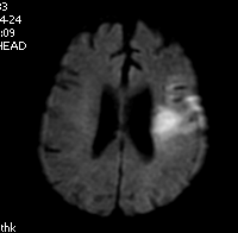

一 颅脑疾病:对脑血管疾病(脑梗死、出血、动静脉畸形、动脉瘤等)、脑肿瘤、炎性病变、脑白质病变、退行性病变及先天畸形具有明确优势。

MRA示右基底动脉开窗 DWI示急性脑梗死